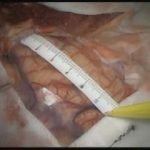

術中写真

摘出 前

摘出 中

摘出 後